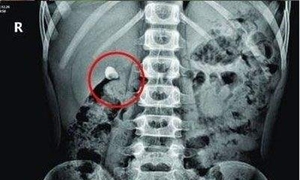

2、肾系B型超声波检查或X线腹部平片、肾盂造影

可明确结石部位。必要时作膀胱镜检和逆行造影。